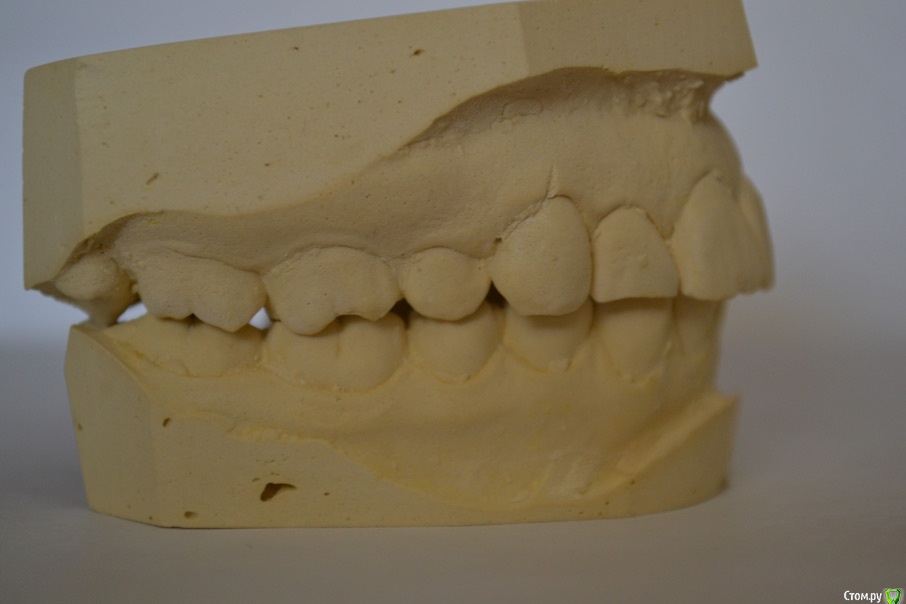

Здравстуйте! Мне 23 года.  У меня смещен центр верхней челюсти вправо и нижней влево. Больше беспокоит меня верх. На верхней челюсти, справа, отсутствует второй премоляр. На нижней клык слева. Премоляр мне в детстве удалили, он рос сверху зуба. Про нижний клык не помню. Проходила лечение не пластинке, не помню, к сожалению, почему. Очень хочу исправить эту ситуацию с зубами, но боюсь решиться, хочется получить гарантию от доктора, что все будет хорошо. Была на 3-х консультациях. На двух сказали что центр сместить нельзя. На одной доктор сказала, что нужно удалить сверху премоляр слева и снизу клык справа. Меня  интересует можно ли это исправить и каким методом, обязательно ли с удалением. Буду очень благодарна за помощь!!

1. с какой целью Вы хотите лечиться? только из-за средней линии??? это не мотивация к долгому трудному и недешевому лечению.  Ситуация в полости рта , конечно,  далека от идеальных зубных взаимоотношений , но с этим можно жить!  если нет явных жалоб на функцию, то часто оставляют как есть, природа сама всё скомпенсировала.

2. если все-таки хотите лечиться, то всё реально, только нужно запастись терпением.  Удалить все восьмерки, выставить средние линии, и  поставить импланты в область недостающих зубов.  Это вариант - максимум.

3. если хотите вариант минимум и просто что-то удалить наверху ради средней линии - то я бы не рекомендовала бы вообще тогда что-либо делать! сейчас у Вас всё скомпенсировано, а после ТАКИХ удалений очень высокая вероятность что начнутся уже реальные проблемы! да и с эстетической точки результатом Вы вряд ли останетесь довольны.